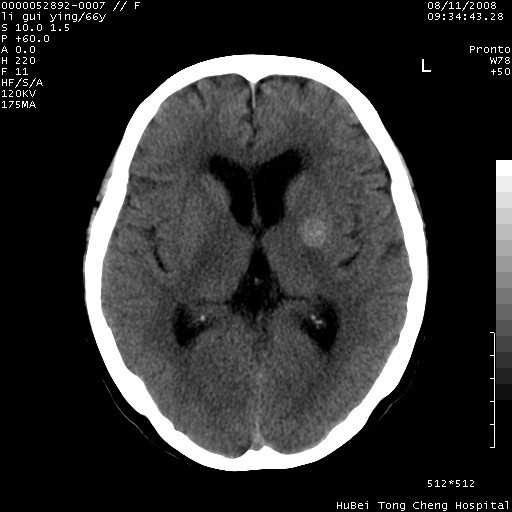

以下是引用sdzyy在2008-8-12 9:59:00的发言:[br]血管瘤可能性大

以下是引用代课学生在2008-8-12 9:48:00的发言:[br]考虑出血灶可能性大。

以下是引用yangyudong333在2008-8-12 12:22:00的发言:[br]1.病灶呈圆形[br]2.周围无水肿带[br]3.密度不均匀,内有点状钙化[br]4.无占位效应[br] 考虑良性占位性病变,血管瘤可能性大